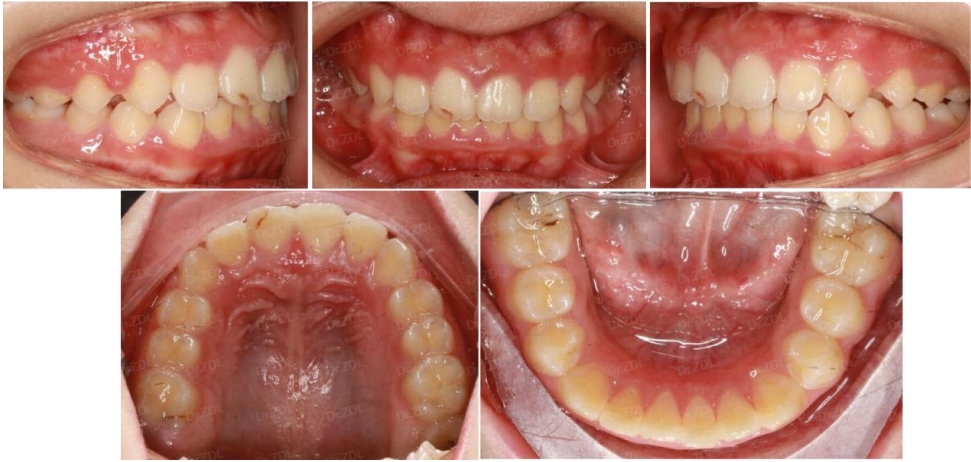

佩戴 Grace24 个月,上颌内收,下颌前伸,上下颌乳牙完全替换完成,牙弓形态正常,牙齿排齐良好,前牙正常覆合覆盖。

因此在早期矫治中,需要密切观察患者的生长发育趋势,利用生长潜力,有效治疗或者缓解错颌畸形的严重程度。孩子如果矫治意愿强烈,配合度高,也是早期矫治成功的重要条件。